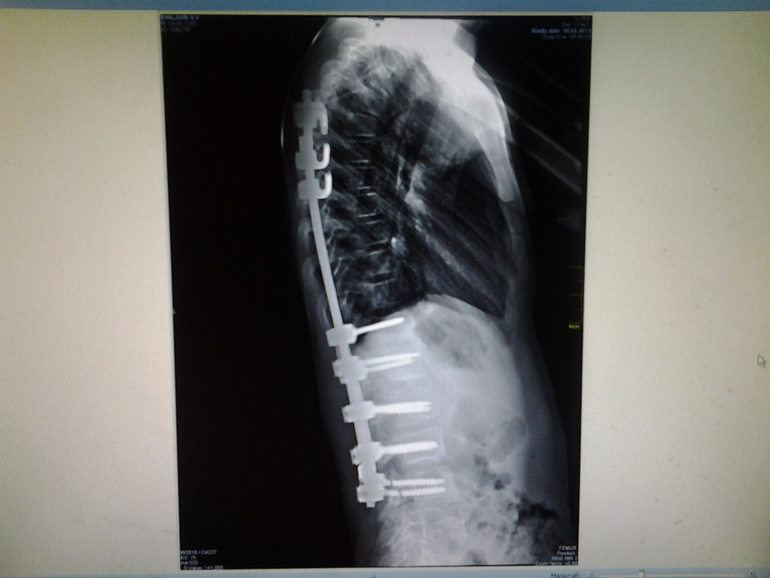

Наши новые снимки!Шурупы то на месте!!!